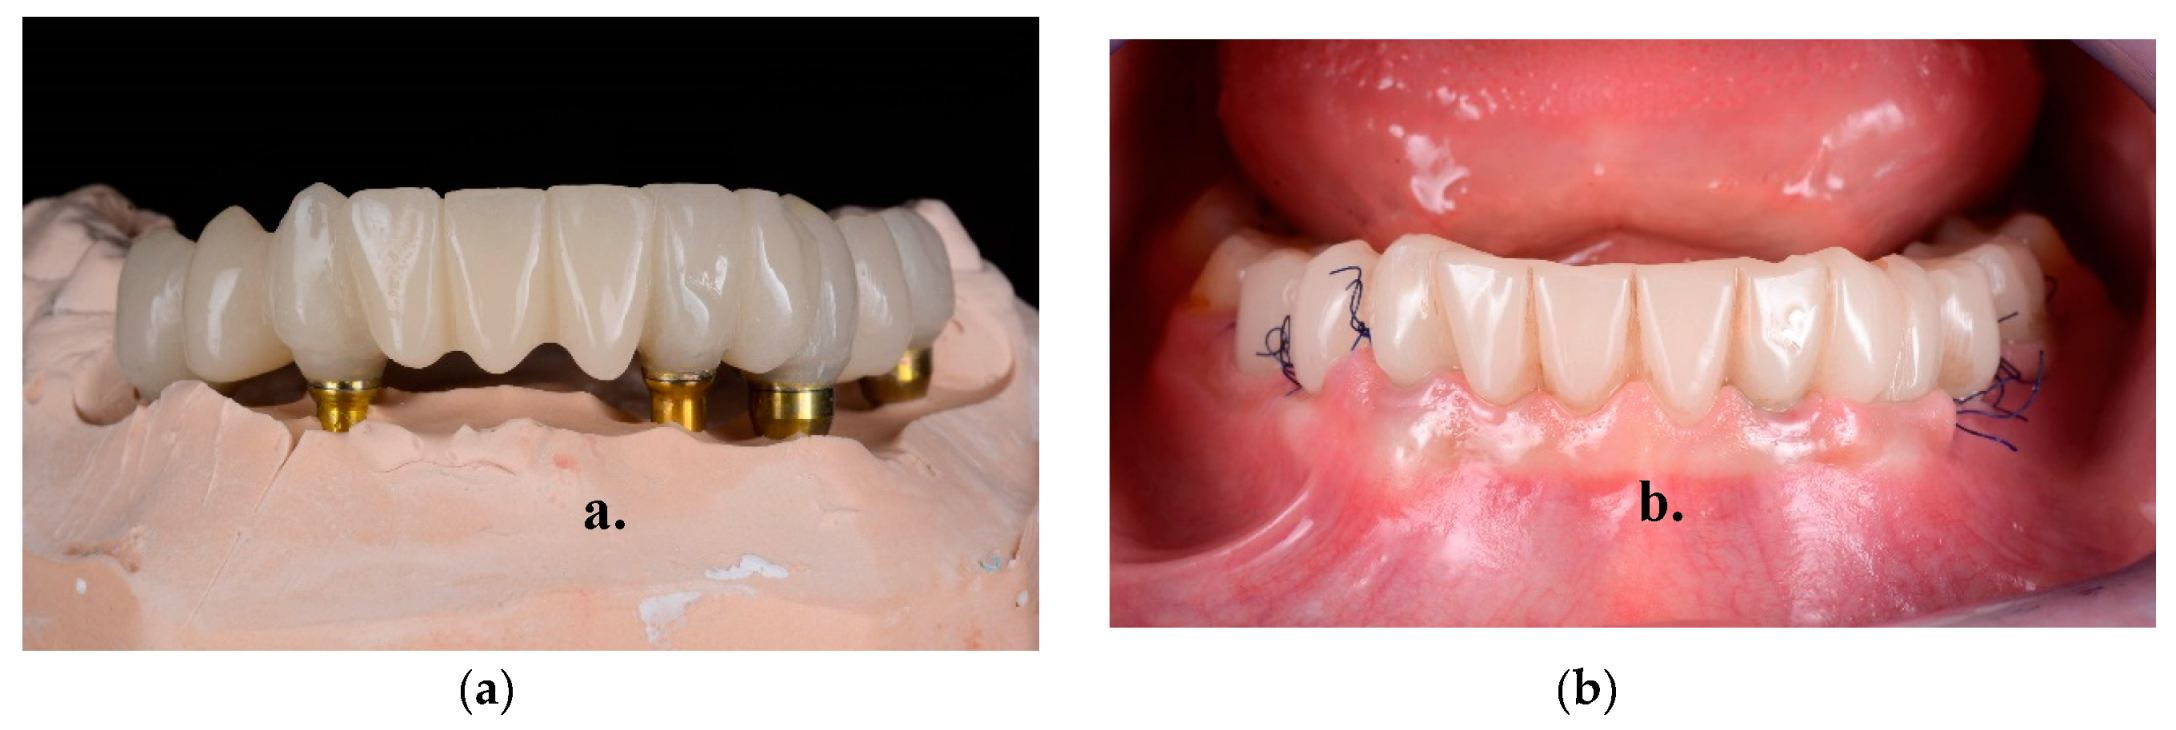

- Final restorations placement